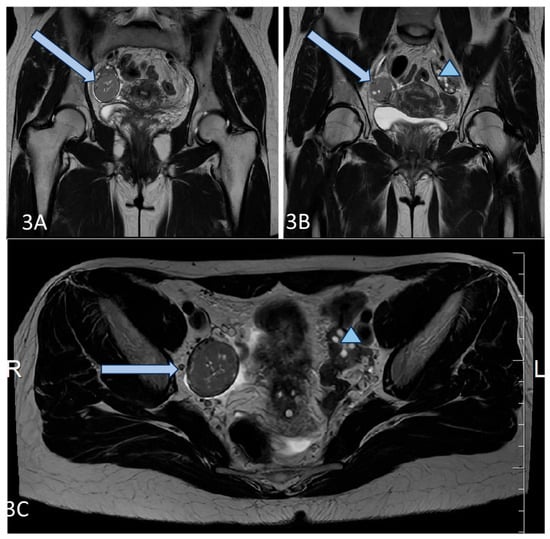

A 36-year-old lean Caucasian female patient (BMI 22.6 kg/m2) with PCOS was referred to the Endocrinology Department. The patient complained of mild hirsutism and oligomenorrhea since menarche (age 17 years). Despite chronic anovulation, she conceived spontaneously several times (two miscarriages and two live births). Increased LH and AMH levels (varying up to 50 ng/mL by unspecified analyses) as well as ultrasound evidence for polycystic ovaries were found by secondary care evaluation, and therapy with oral contraceptives was started. The patient had regular menstrual bleeding on therapy, but decided to stop the pill, leading to continuous amenorrhea, attributed to her PCOS, for several years. In 2021, the investigations in the Endocrinology Department showed normal testosterone and estradiol levels, increased LH and AMH (Table 1), as well as normal tumor markers (Ca-125, HE4). A pelvic ultrasound by an experienced gynecologist suggested 2/2 cm formation of the right ovary and no pathological findings of the left ovary. Magnetic resonance imaging (MRI) and laparoscopy were recommended because of a suspected fibroma/granulosa cell tumor, but the patient refused further investigations. Two years later, she performed the recommended MRI and a solid tumor 42/38/35 mm was described (Figure 3). She repeated her hormonal tests because of persisting amenorrhea, and again increased LH and AMH levels and normal androgens were detected (Table 1).

Figure 3. (AC) Axial T2 (A,B), and Coronal T2 (C) images of the patient demonstrate a well-circumscribed mass, representing a solid granulosa cell tumor at the level of the right ovary (blue arrow), and normal size and appearance of the left ovary (blue triangle).

The patient agreed to an operation, and a right ovariectomy was performed in the University Hospital of Obstetrics and Gynecology “Maichin dom”, Sofia, Bulgaria. A 5 cm large ovarian tumor was removed, and the histological evaluation confirmed the granulosa cell tumor—adult type. The patient was sent to an oncologist, but refused additional chemotherapy or surgery. One year after the operation, she had regular menstruation, and normal AMH and LH levels (Table 1).